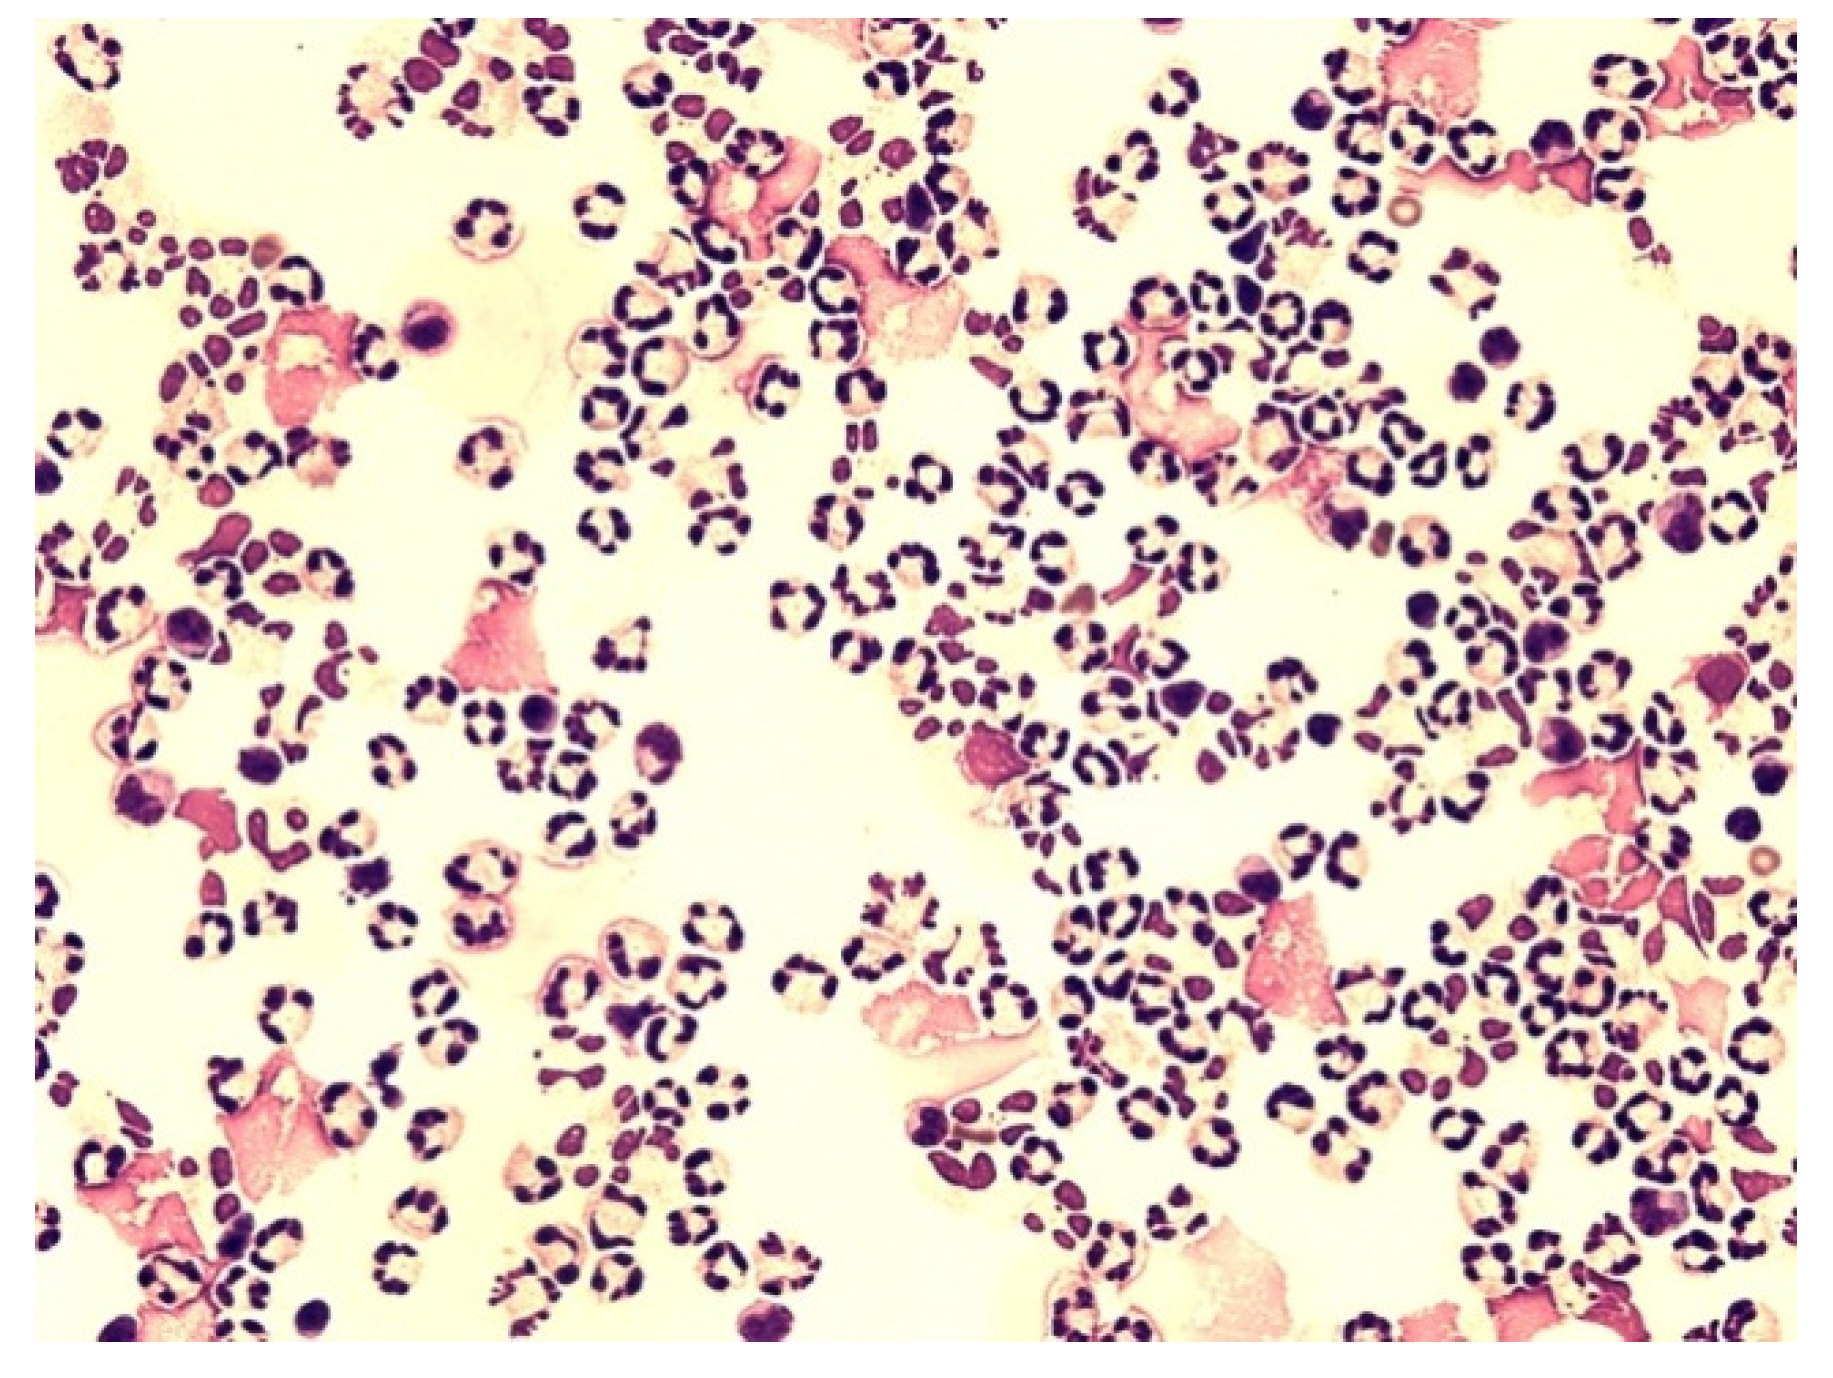

Figure 6.

Predominance of neutrophils in the cerebrospinal fluid; KEB = 22.9; non-purulent inflammatory reaction in the CNS of patients caused by subarachnoid hemorrhage.